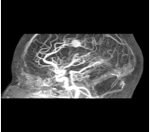

A: PRE-SURGICAL IMAGES

MRi 3T CT-scan